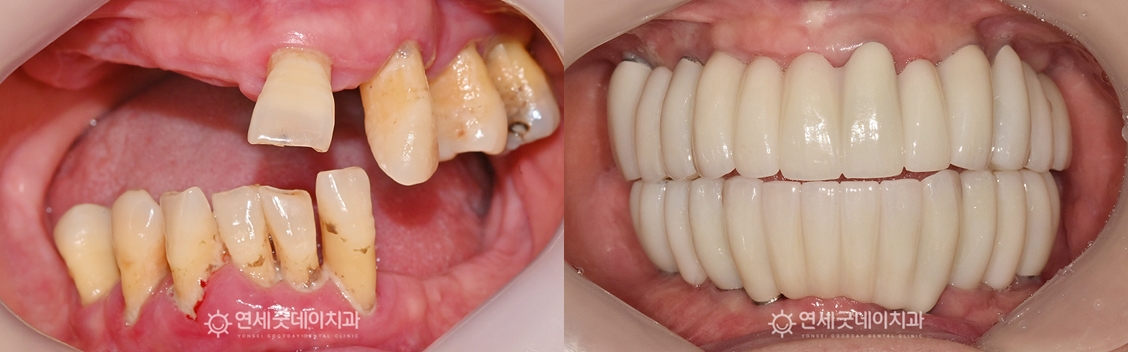

전체임플란트 및 상악동수술 치료전후 (50대)

전체임플란트 식립 이후 보철 제작 단계에서도 또한, 환자분의 니즈를 반영하여 치아 모양과 길이,

치료 마무리 후에는 스마일라인이 자연스러워지고